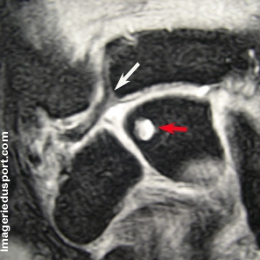

B - IRM du poignet droit, coupe coronale T2 : La formation géodique du lunatum est en hypersignal relatif net. Remaniement dégénératif du disque articulaire du TFCC qui apparait en hypersignal relatif mais sans fissure communicante visible.

C - IRM du poignet, coupe axiale T2 protons : La formation géodique du lunatum est en hypersignal relatif net. Elle apparait de siège palmaire.